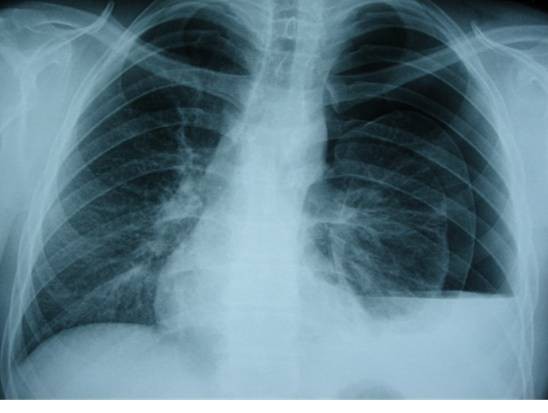

Pneumocystis jiroveci-Pneumonie: AIDS bei HIV-Infektion (oben Thorax pa, unten Thorax-CT) |